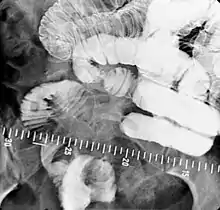

X-ray images are then taken in a supine position at intervals of 20–30 minutes. Real-time fluoroscopy is used to assess bowel motility. The radiologist may press or palpate the abdomen during images to separate intestinal loops. The total time necessary for the test depends on the speed of bowel motility or transit time and may vary between 1 and 3 hours.[17]